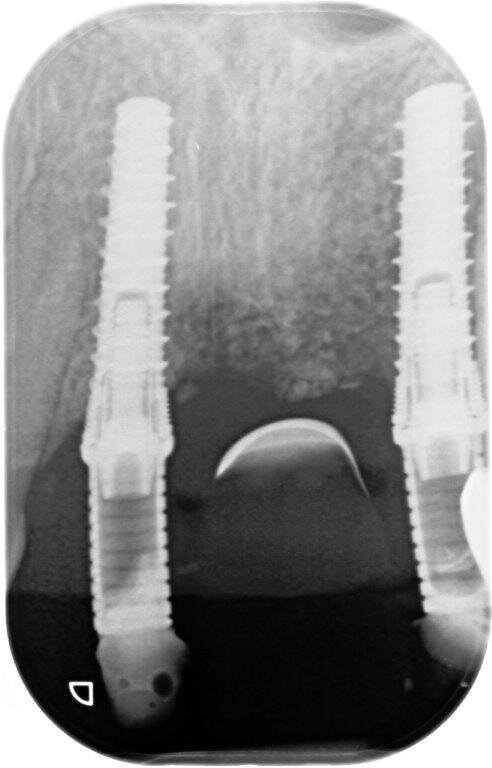

A 9 mesi è stata effettuata la seconda fase chirurgica in cui era prevista la rimozione delle viti di osteosintesi e il posizionamento degli impianti nei siti 1.1 e 1.2 (Blossomâ Intra-Lock System Europa). Grazie al volume osseo rigenerato risultava adeguato il posizionamento degli impianti come da progettazione protesica iniziale (Figg. 16-19).

Fig. 13 - Valutazione del sito rigenerato all’esame radiologico.

Fig. 17 - Preparazione del sito implantare; impianti Blossom Intra-Lock.

Fig. 22a, 22b - Valutazione dei tessuti duri e molli perimplantari.